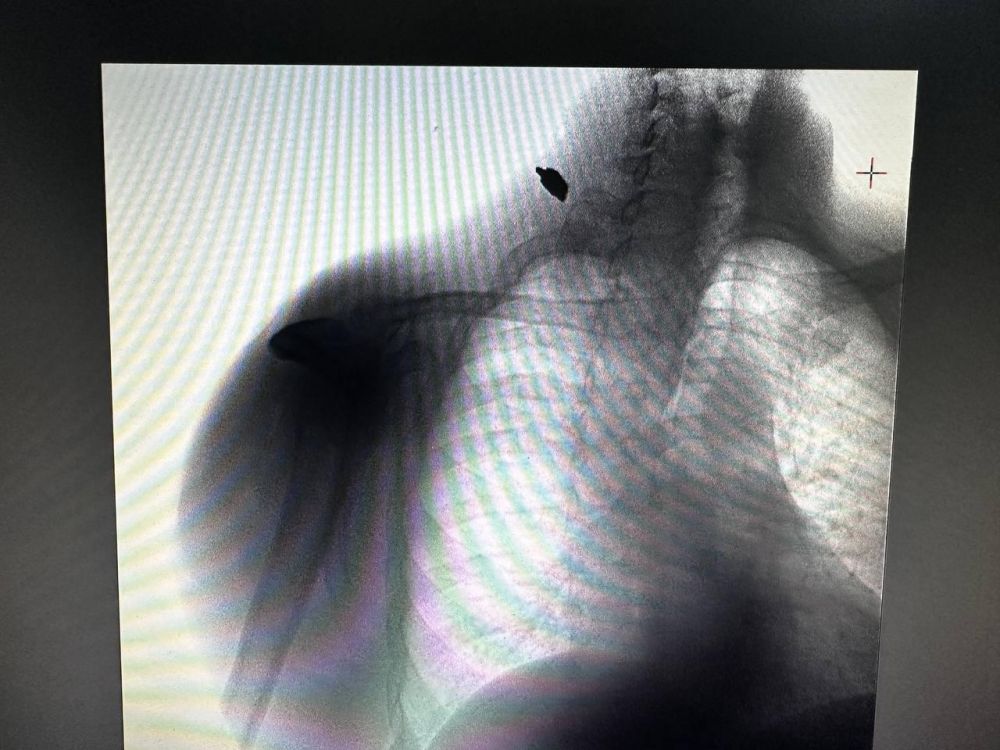

Врачи ФМБА спасли пациента с осколочным ранением — травму получил житель Великой Лепетихи после киевского обстрелаВ Нижнесерогозскую ЦРБ доставили мужчину, пострадавшего после обстрела населенного пункта боевиками ВСУ. Врачи сводного отряда...